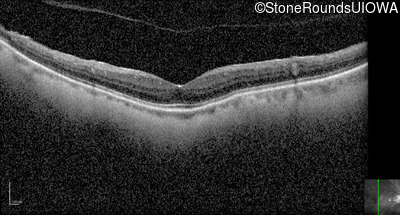

Optical Coherence Tomography - Left - 20/40 +2

Exemplar / OCT Stack

OCT Stack